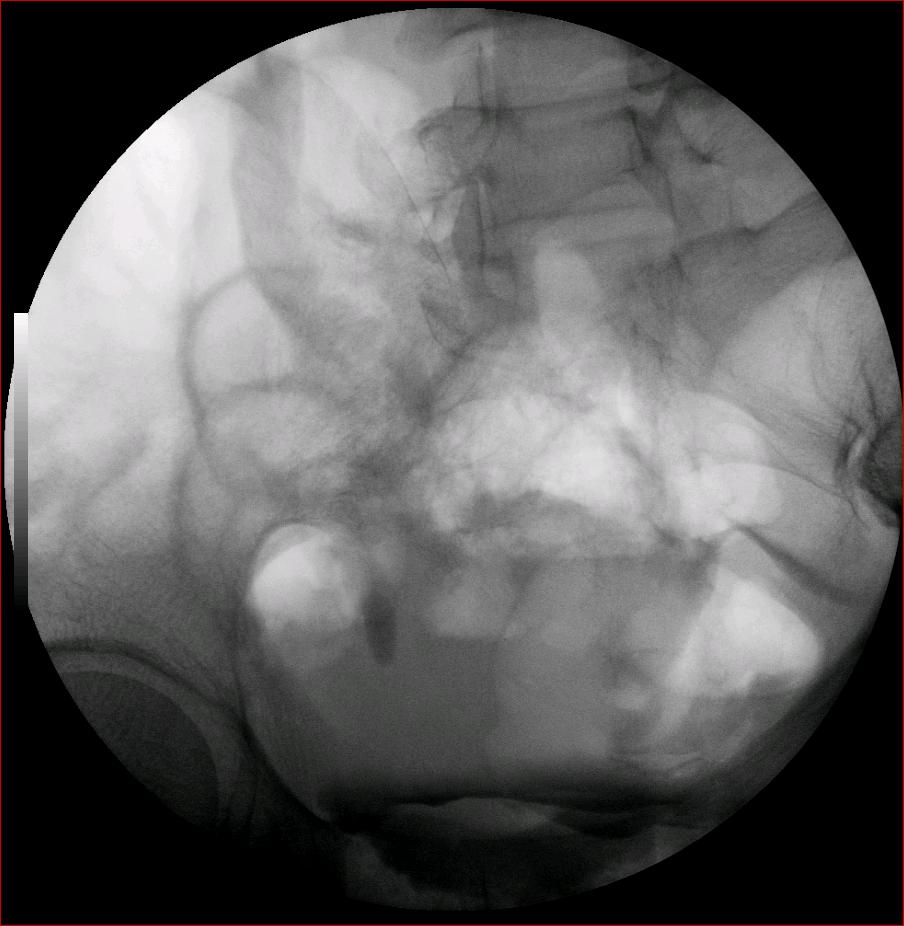

以下是引用luoxinjun在2008-2-18 15:54:00的发言:[br]右肾积水,右输尿管下端结石

以下是引用zhangxiangjun在2008-2-18 21:01:00的发言:[br]右输尿管盆段末端结石,继发其近端输尿管、右肾积水。

以下是引用hexue在2008-2-18 17:33:00的发言:[br]右输尿管下段结石并右肾及右输尿管积水扩张

以下是引用杀毒软件在2008-2-18 16:24:00的发言:[br]右输尿管下段结石,肾盂积水。